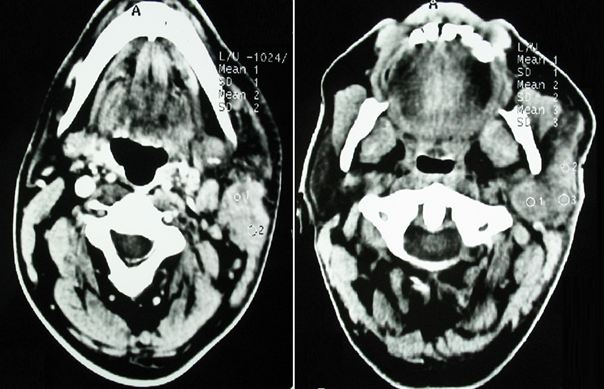

Parotid ultrasound showed an enlarged parotid with a heterogeneous tumor, poorly defined, and hyper vascularized on Doppler, associated with multiple satellite adenopathies (Figure 1). Computed tomography (CT) scan showed a parotid swollen by a parenchymal tumor, hypodense, heterogeneous, and enhancing heterogeneously after injection of contrast product. This tumor infiltrated the peri-parotid fat with multiple adenopathies of secondary appearance (Figure 2 & 3).

Figure 1 Cervical ultrasound: Heterogeneous tumor of the left parotid gland (A) with multiple enlarged lymphatic nodes (B).